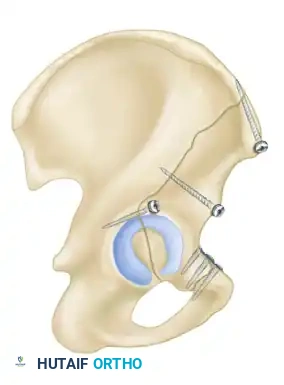

The Modified Stoppa Approach

- Indications: Medial displacement of the quadrilateral surface, anterior column fractures, and certain both-column fractures.

- Positioning: Supine.

- Technique: A transverse Pfannenstiel incision is made, and the surgeon works intrapelvically, deep to the rectus abdominis and along the pelvic brim. This approach provides direct visualization of the quadrilateral plate and allows for the application of medial buttress plates to prevent medial subluxation of the femoral head. It is frequently combined with a lateral window (from the ilioinguinal approach) for complete anterior column access.